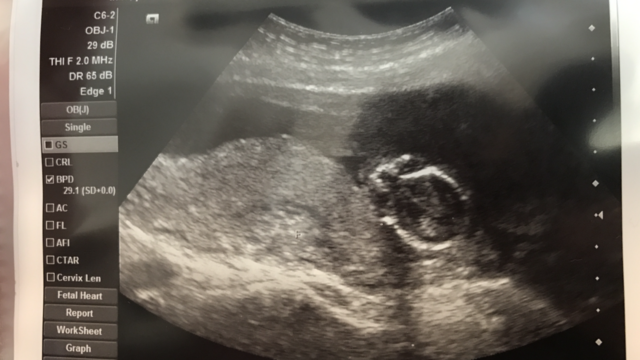

14週4日(14w4d・性別不明)|みさき831 さん(23歳)

エコー写真撮影時のエピソード:

13週のエコー写真では、初めて超音波エコーによって顔・首・体が見えて感動しました。人間らしい形を見ることで、赤ちゃんを妊娠している実感が湧きました。生理不順だった為、赤ちゃんは少し小さいようです。これから、しっかり栄養を摂って赤ちゃんに大きくなってもらいたいです。

体調の変化は、これまで物をあまり食べられなかったのが、食べられるようになり、2時間おきにお腹が空くようになり困っています。